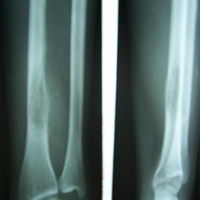

Case:3 Ewings Tibia

Pre-Op

Post-Op